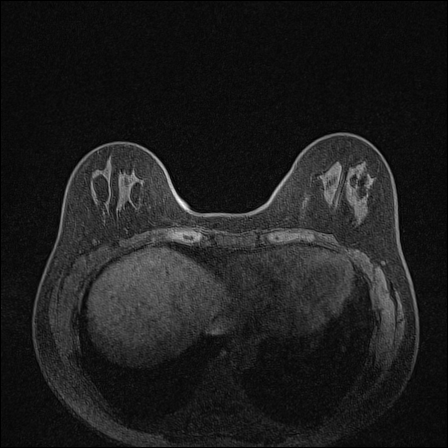

MRI images. The data used in this study are from the DUKE Breast Cancer Dataset [23], a comprehensive single-institutional retrospective collection of 3D MRI scans from over 900 patients with biopsy-confirmed invasive breast cancer at a university hospital. Each study includes a 3D MRI acquired using 1.5T or 3T scanners, from patients in the prone position. On average, each 3D scan consist of 250 2D slices (see Figure 1). For the predictive tasks, the slices are categorized into two groups: those containing breast tumors and those without. Following the approach of [15, 12], we establish a buffer zone between slices containing tumors and those that do not (highlighted in yellow in Figure 1(a)). Images within this buffer zone are excluded from analysis, and the remaining slices are labeled and used for the predictive task.

Magnetic field strength. 3T scanners offer higher magnetic field strength, improving signal-to-noise ratio (SNR) and image resolution for sharper, more detailed images [24]. However, they are more prone to artifacts, heating effects, and signal loss, especially around metal implants [5]. As such, our proposed dataset involving this spurious signal features a non-local spurious signal that influences the entire image rather than a localized region. An example set of images obtained from 1.5T and 3T devices are provided in Figure 3, showing that it is visually not possible to distinguish 1.5T MRIs from the 3T ones.

Vertical orientation. Different from magnetic field strength, which affects the entire image globally, vertical orientation is a local feature that only alters the spatial arrangement of structures within the image. This transformation does not modify the underlying tissue characteristics or signal properties but instead introduces artificial correlations that models may exploit as shortcuts.